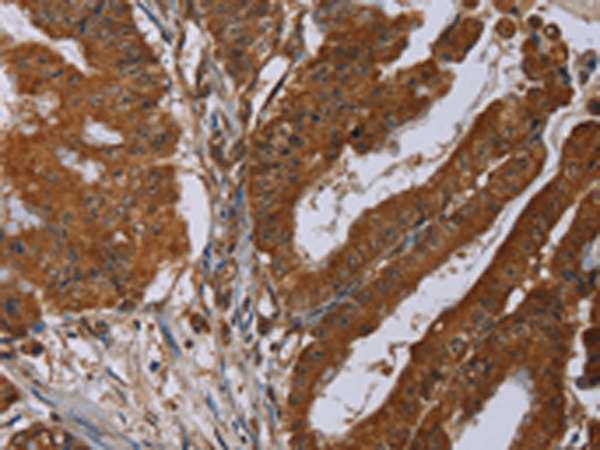

分类: 科研抗体货号: P05034别名: CT7; CT7.1应用: IHC反应种属: Human